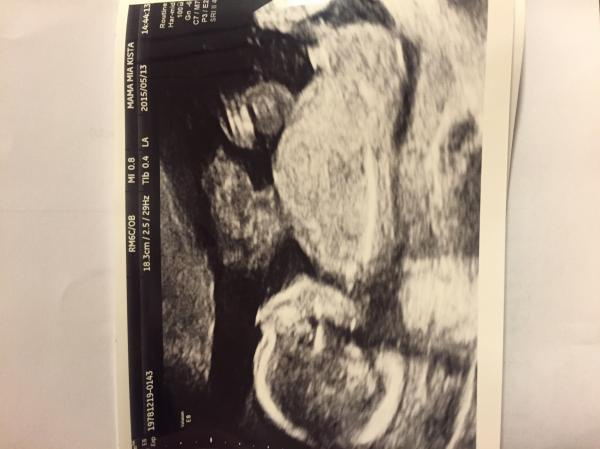

Gjorde RUL igår. 15/10 fick jag så det blev en flytt på 5 dagar. Skönt!

Vi har rul 28 maj, spännande! På kub-ultrat räknade bm 24 okt, men läkaren som gjorde fvp tyckte det kunde vara några dagar 'yngre' än så. Får se vad de säger på rul!

Det är så kul att se era RUL, vill också! Har inte förrän 2 juni :)